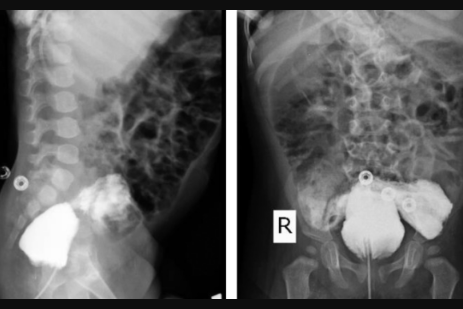

A equipe médica realizou exames por mais de um ano após o nascimento da criança para entender como funciona o sistema urinário raro do paciente. Por meio de exames de imagem, foi identificado que o menino possui uma fístula, ou seja, uma ligação anormal entre a bexiga e o reto - que fica no final do intestino.

image Exames de imagem do recém-nascido (Reprodução: Radiology Case Reports)